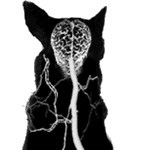

New research lead by the Royal Veterinary College (RVC) canine epilepsy clinic working together with world-experts in the field has highlighted the difficulty of diagnosing seizures in dogs and cats from videos recorded by pet owners on mobile devices.

Study also finds the importance of additional clinical information alongside videos to make a diagnosis, and the need for robust seizure classification systems to differentiate between seizure types